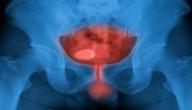

يعرف الخدران Numbness بأنه حالة صحية غير طبيعية تتمثل على شكل وخز أو فقدان في الإحساس في منطقة معينة، ويمكن أن تحدث هذه المشكلة في أي جزء من أجزاء الجسم، ولكن تشاع هذه المشكلة في الآتي:[١]

الأسباب المتعلقة بالدورة الدموية

تؤثر العديد من المشكلات الصحية على الدورة الدموية، حيث يمكن أن تتسبب بضعف فيها الأمر الذي ينتج عنه الشعور بالخدران والوخز نتيجةً لعدم وصول كميات مناسبة من الدم إلى هذه الأجزاء، وغالبًا ما تكون الأطراف، ومن أبرز مشكلات الدورة الدموية وأكثرها شيوعًا والتي تسبب الخدران الآتي:[٧]

• تصلب الشرايين.

• داء السكري.

• جلطات الدم.

• مرض رينود.

• زيادة الوزن.